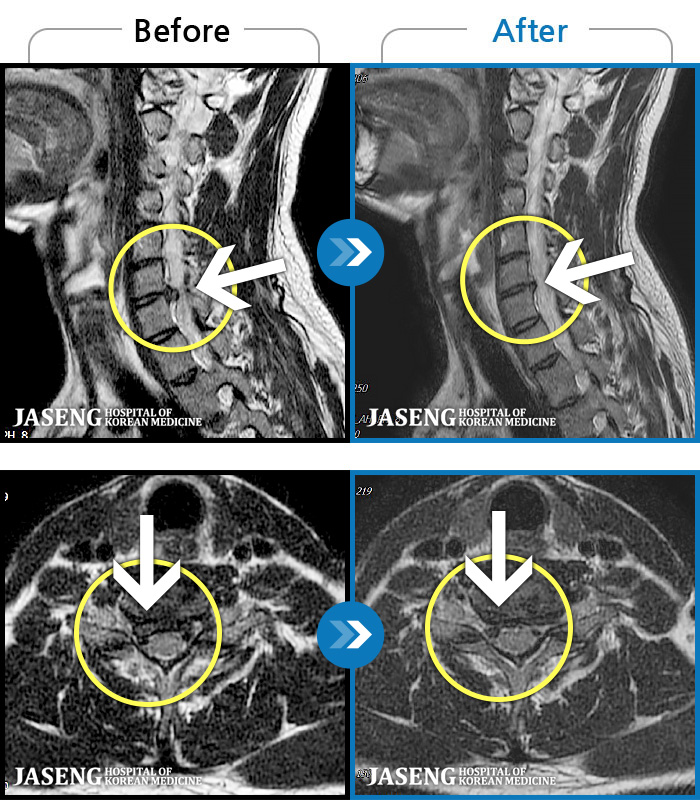

- MRI ġ

MRI ġ

1,304 MRI ũ ʸ Ȯϼ.